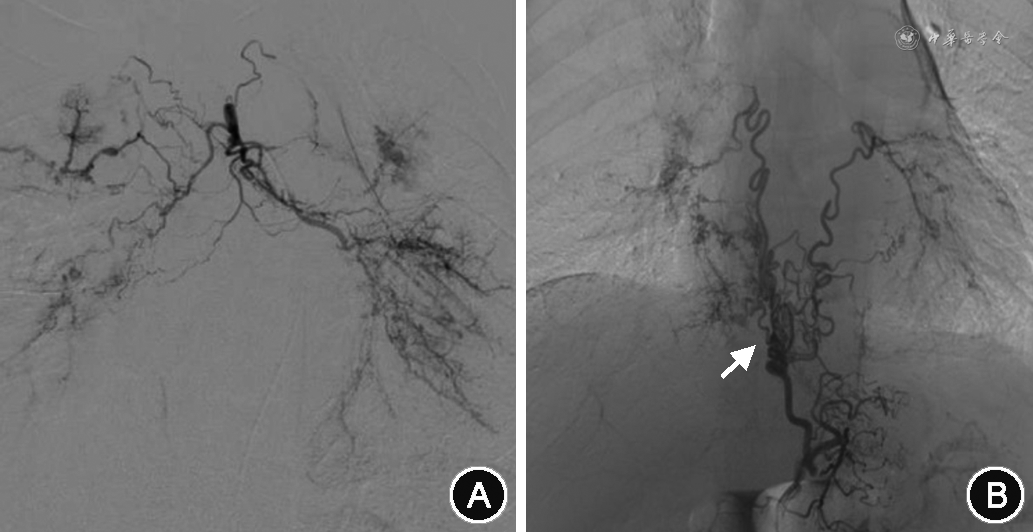

所有患者术中DSA均发现支气管动脉(bronchial artery,BA)血管增粗、迂曲,末梢分支增多紊乱,病灶区域血管呈网状或丛状分布(图2A),其中,29.6%为异位起源BA(图2B)。774例(63.9%)患者存在非支气管性体动脉(non-bronchial systemic artery,NBSA)异常并参与病灶部位供血(图2C)。1 092例(90.2%)患者存在体动脉-肺循环异常交通。包括肋间动脉-肺动脉瘘(图2C),食管固有动脉-肺动脉瘘(图2D);BA-肺静脉瘘(图2E);肺动-静脉瘘(图2F);143例(11.8%)有动脉瘤或瘤样扩张。包括支气管动脉瘤(图2G);非支气管性胸廓内动脉瘤(图2H);肺动脉假性动脉瘤(图2I)。单纯肺动脉高压引起的咯血,以第一大类先天性心脏病引起的肺动脉高压为常见,责任血管可涉及锁骨下动脉分支、胸、腹主动脉分支(支气管动脉、肋间后动脉、膈下动脉、食管固有动脉),主干迂曲增粗、末梢紊乱,责任血管床大多沿肺门周围分布(图3)。白塞病的靶血管分布在以肺动脉灌注较差位置的周围体动脉的迂曲、扩张及末梢紊乱,多发的体-肺动脉瘘形成,责任血管末梢网血管丰富(图4)。